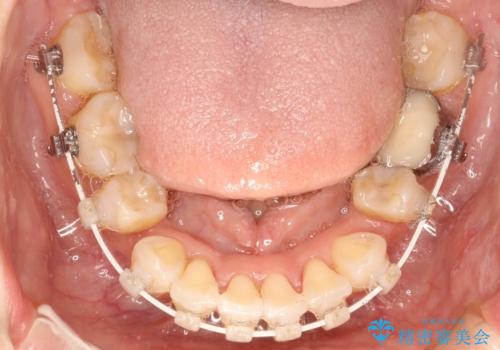

- 矯正装置

- 審美装置

上下左右の歯を1本ずつ抜歯して、ワイヤーにて矯正を行いました。

かみ合わせの深さを改善するのに時間がかかり、予定よりも治療期間が長期化しましたが、整った歯並びへ改善することができました。